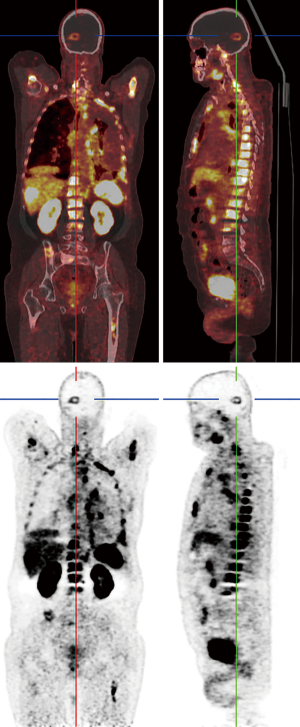

Recently, novel PET-tracers have been developed which have demonstrated better results than 18F-FDG PET imaging (5,6). Among them, radiolabeled amino acids have shown promising potential in accurate tumor volume delineation, active metabolic volume, and better results in pre-surgical or pre-radiotherapy planning (5,6,14). An investigation revealed that the utility of hybrid imaging through fusing amino acid PET (or SPECT) with MR (or CT) imaging in the reirradiation planning of recurrent high-grade gliomas significantly improved survival time compared with CT or MR imaging alone (14). Investigators recruited 44 participants with recurrent high-grade gliomas after previous surgical resection and adjuvant conventional radiotherapy ± chemotherapy (temozolomide). For treatment planning of fractionated stereotactic radiotherapy (FSRT), the gross tumor extent was delineated using hybrid imaging modality through fusing 123I-methyl-tyrosine (IMT) single-photon computed emission tomography (SPECT) or 11C-methionine positron emission tomography (MET-PET) with computed tomography (CT) or MRI in 82% of the subjects and by CT/T1gadolinium-MRI image fusion in 18% of them (Figures 1,2). Results showed that treatment designing using fused PET (SPECT)/MR (CT) imaging was correlated with the improvement of survival compared to treatment designation based on CT/MRI alone.